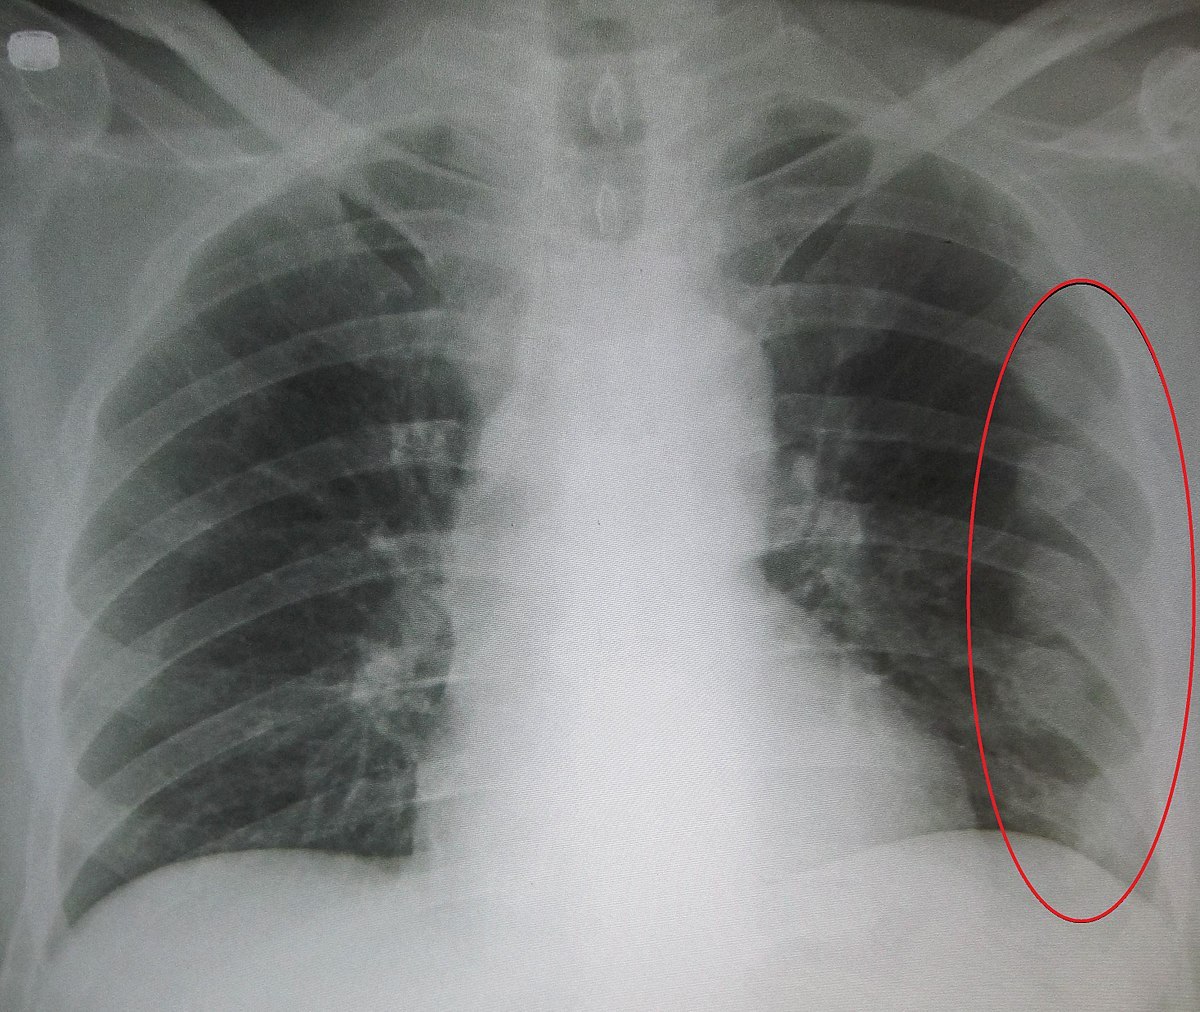

병원에도 물론 가봤다. 어느날 닥터페퍼 색깔의 혈뇨가 나오길래 화장실 조명이 이상한가 생각했지만, 그 다음날에도, 또 그 다음날에도 혈뇨가 계속되어 결국 내과에 갔다. 혈액 검사, 엑스레이, 초음파 등 다양한 검사를 동원했으나 이상을 찾지 못했다. 다만, 소변에 혈액이 섞여 나오는 증상은 확실했으므로, 의사는 나를 비뇨기과로 보냈다.

그러나 비뇨기과에서도 아무런 이상을 찾지 못했다. 통증 위치가 갈비뼈 끝나는 지점 내지 그 바로 아래였기 때문에 신장 쪽의 이상을 강력하게 의심했으나, 의사의 말은 신장이 매우 깨끗하다는 것이었다. 결석을 의심할 수도 있다고 했는데, 나는 요로결석을 앓아본 경험이 있어서 그 통증과는 전혀 다른 통증이라고 말했다. 비뇨기과 의사는 근육통이 원인일 수 있다며 나를 정형외과로 보냈다.

정형외과에서도 딱히 이유를 찾지 못했다. 이미 내과 검진 때 엑스레이를 찍은 상황이고, MRI나 CT를 찍는 건 과한 일이었다. 나중에 '통증의학과'라는 병원이 동네에 있어 찾아가 보았는데, 그냥 정형외과였다. 의사는 비뇨기과를 다시 가보는 것을 추천했다.